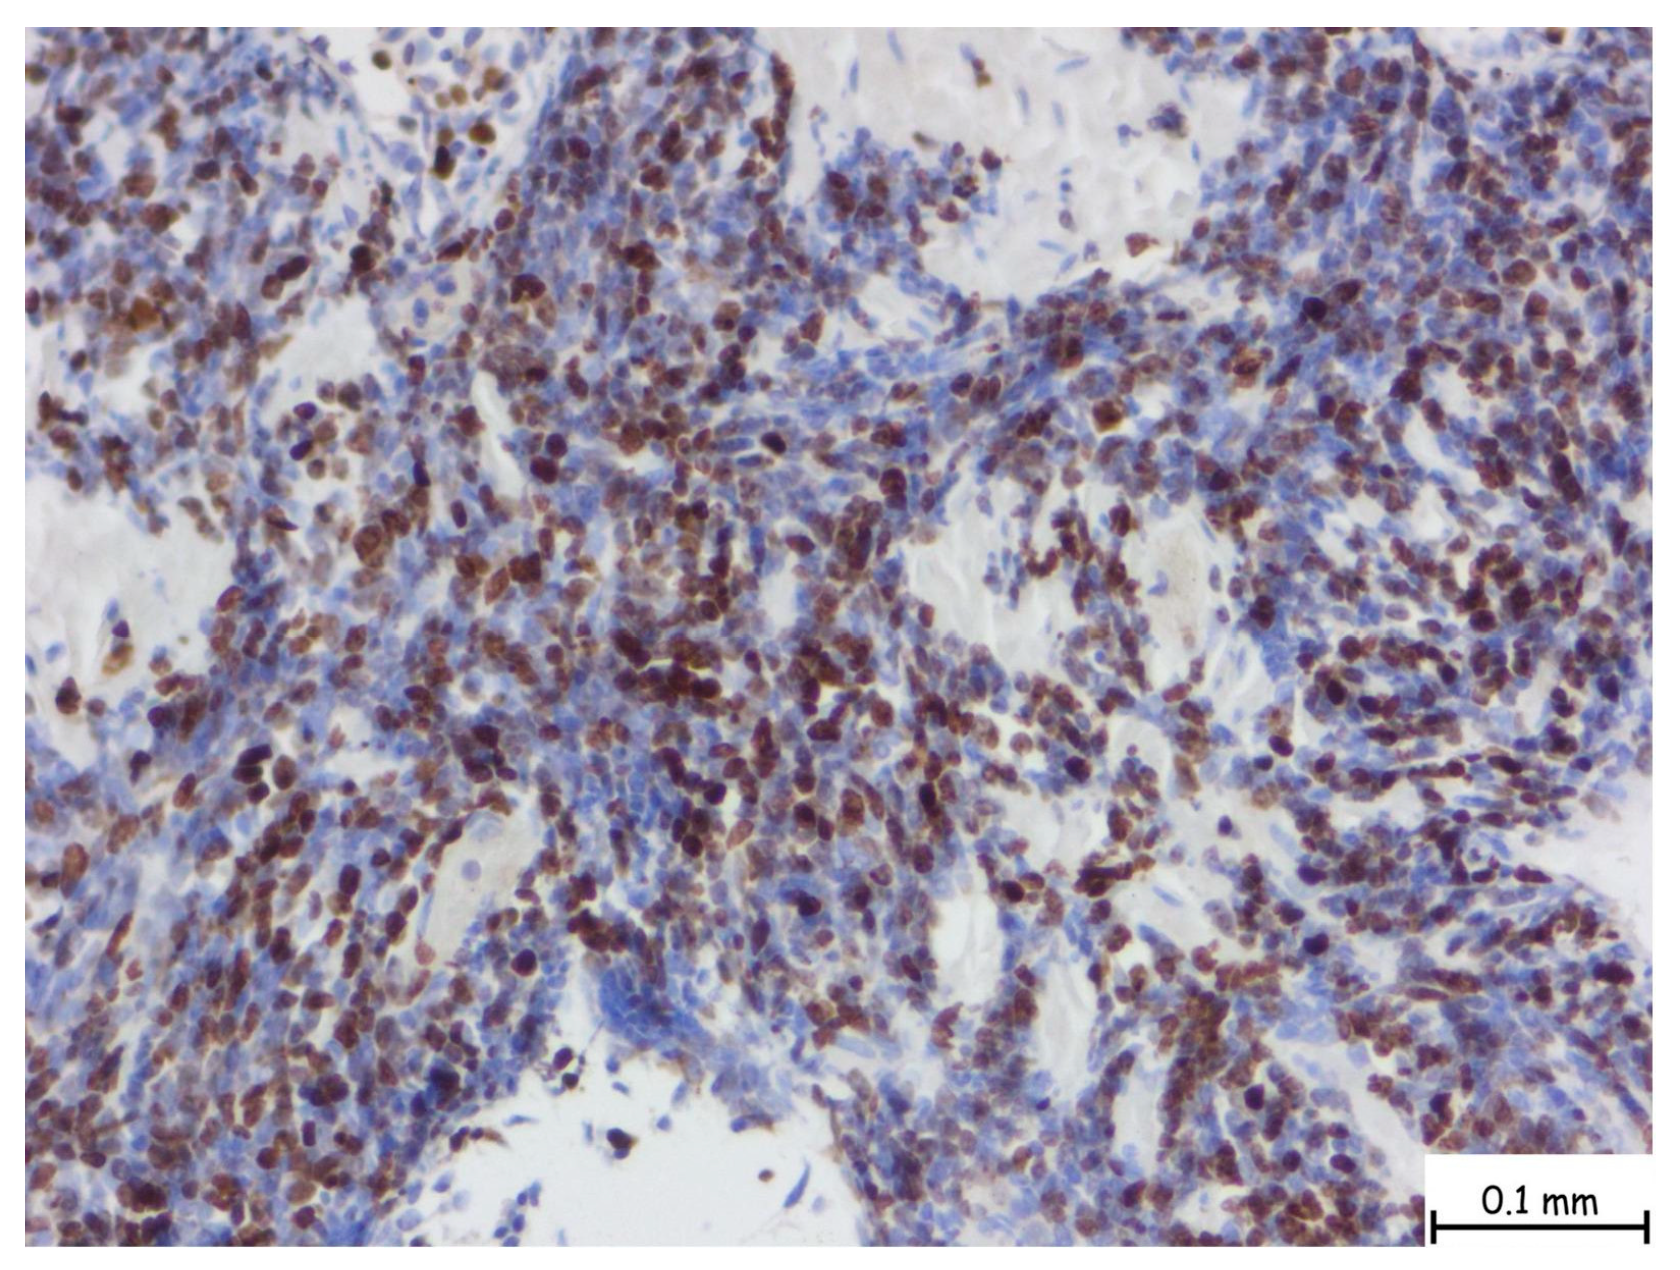

The microscopic examination revealed a lymphoproliferative process characterized by a diffuse lymphoid infiltrate, with focal areas displaying a vaguely nodular structure. The infiltrate consisted of medium-sized cells, among which, large cells with slightly irregular nuclei and no prominent nucleoli were consistently observed. This process involved nearly all examined tissue fragments and disrupted the glandular architecture of the prostatic parenchyma (Figure 2a–d). Immunohistochemical staining with CD20 confirmed a mature B-cell origin (Figure 3). The Ki67 proliferation index was 60–70%. Given the patient’s prior histopathological diagnosis, additional immunohistochemical tests were performed to confirm mantle cell lymphoma, including CD20, CD3, Ki67, Bcl-2, Bcl-6, MUM1, Cyclin D1, CD23, CD5, and CD10. The tumor cells exhibited strong and diffuse expression of Bcl-2, CD5, and Cyclin D1, while CD23, Bcl-6, MUM1, and CD10 were not expressed. This immunophenotype is consistent with mantle cell lymphoma (Figure 4).

Figure 4.

The nuclear brown staining pattern is characteristic for Ki-67, a well-established marker of cellular proliferation. In this case, numerous nuclei are positive for Ki-67, indicating a significant fraction of actively cycling cells. The Ki-67 proliferation index is intermediate to high, with an estimated labeling index ranging from 30% to 60% depending on region, suggestive of a more aggressive biological behavior or a higher-grade lymphoma subtype. The microscopic magnification is 40×.